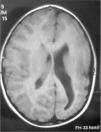

En la resonancia magnética (RM) craneal se evidencia el mayor tamaño del HD, que presenta un área de mayor brillo en T2 y Flair localizada en la sustancia blanca parietal posterior, mayor tamaño de la región derecha del troncoencéfalo respecto a la izquierda y polimicrogiria en el HI, junto con las alteraciones morfológicas ya visibles en la TCC (fig. 4).